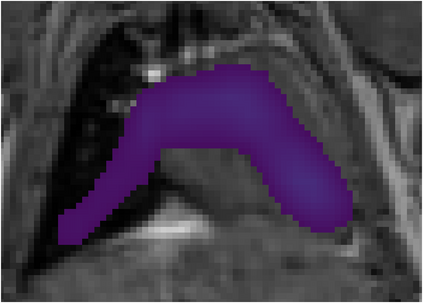

Various imaging modalities allow for time-dependent image reconstructions from measurements where its acquisition also has a time-dependent nature. Magnetic particle imaging (MPI) falls into this class of imaging modalities and it thus also provides a dynamic inverse problem. Without proper consideration of the dynamic behavior, motion artifacts in the reconstruction become an issue. More sophisticated methods need to be developed and applied to the reconstruction of the time-dependent sequences of images. In this context, we investigate the incorporation of motion priors in terms of certain flow-parameter-dependent PDEs in the reconstruction process of time-dependent 3D images in magnetic particle imaging. The present work comprises the method development for a general 3D+time setting for time-dependent linear forward operators, analytical investigation of necessary properties in the MPI forward operator, modeling aspects in dynamic MPI, and extensive numerical experiments on 3D+time imaging including simulated data as well as measurements from a rotation phantom and in-vivo data from a mouse.